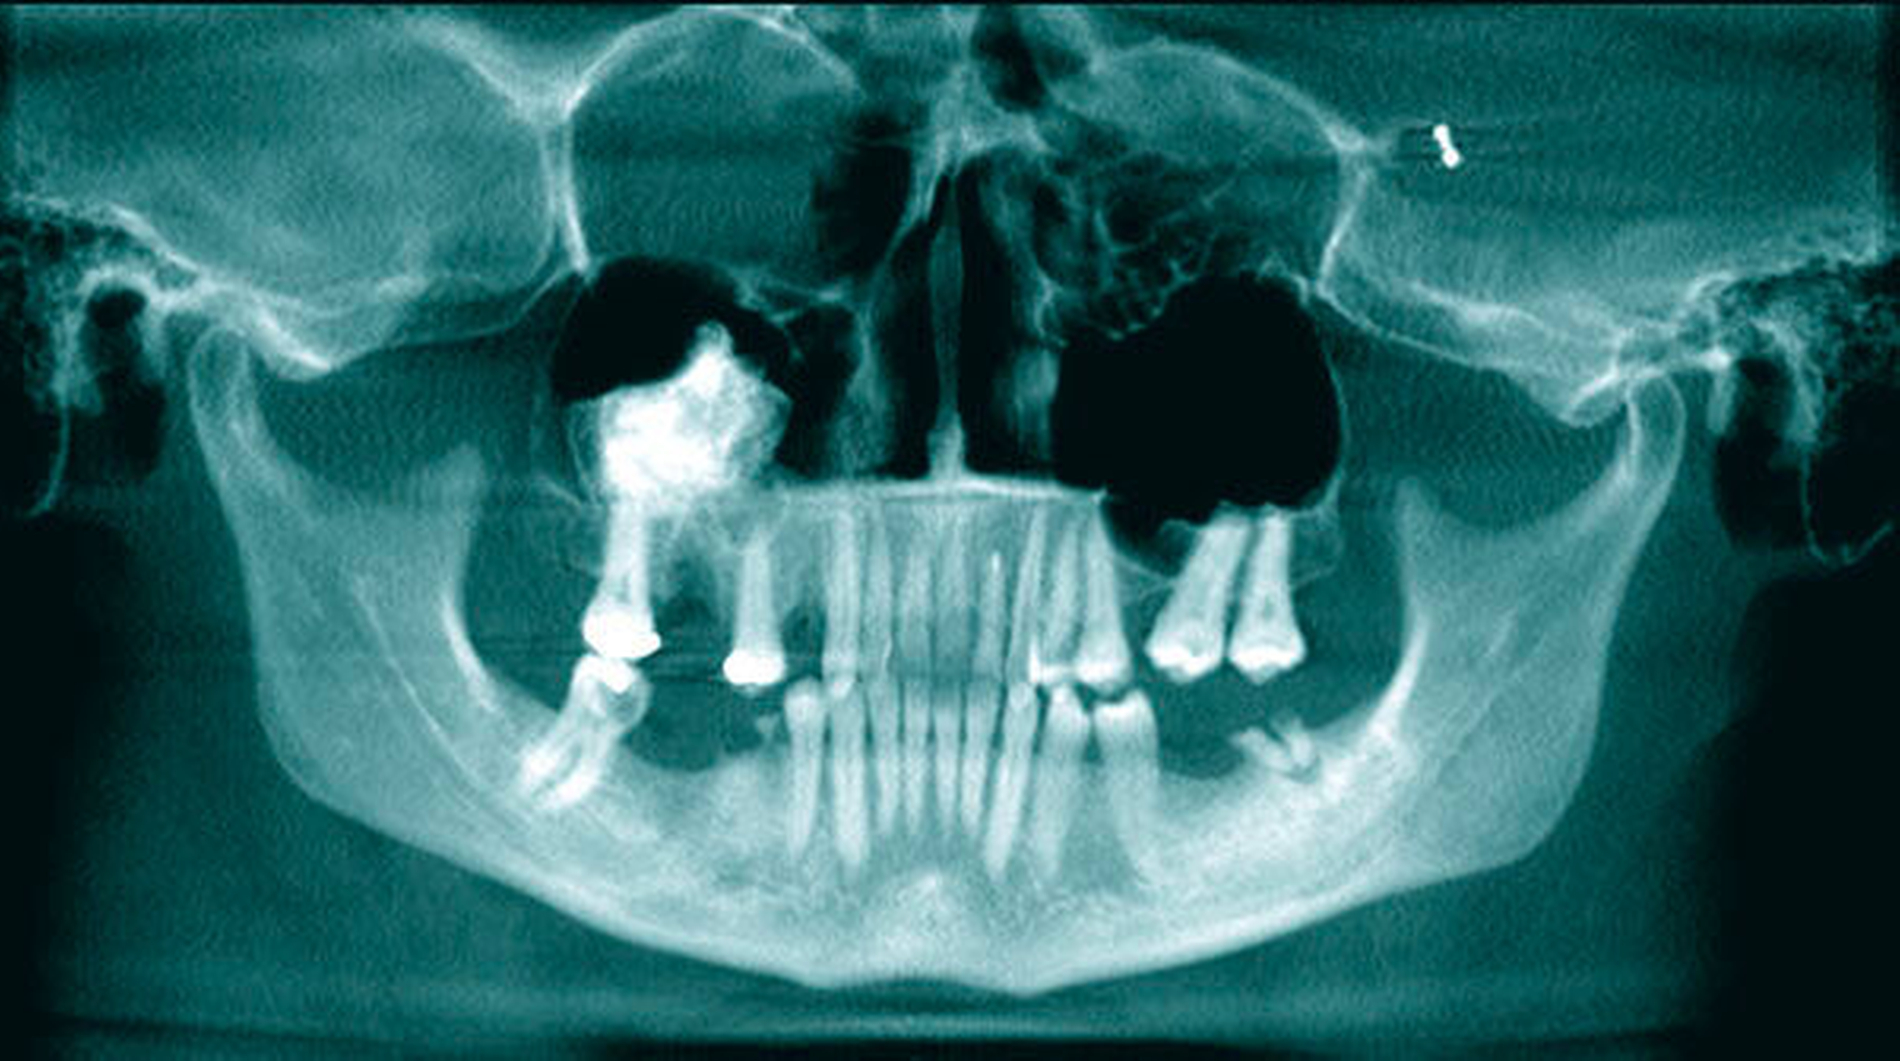

Eine 51-jährige Patientin wurde durch ihren Zahnarzt mit der Frage nach weiterführender Diagnostik an die Abteilung für Mund-, Kiefer, und plastische Gesichtschirurgie der Universität Mainz überwiesen. 14 Tage zuvor war die Frau mit einer rechtsseitigen Schwellung der Wange erwacht, woraufhin sie sich bei ihrem Hauszahnarzt vorstellte. Bei Vorliegen eines Fossa-canina-Abszesses wurde durch den Zahnarzt eine Inzision der Abszesshöhle und die Extraktion der schuldigen Zähne 14 und 16 durchgeführt. In der erstellten Panoramaschichtaufnahme (PAN) fiel ihm eine röntgendichte Raumforderung der rechten Kieferhöhle auf, die von der Universitätsmedizin untersucht werden sollte. Die Anamnese und die klinische Untersuchung zeigten sich unauffällig, so dass zwecks weiterer diagnostischer Analyse eine 3-D-Aufnahme (DVT) des Gesichtsschädels durchgeführt wurde (Abbildungen 1 bis 3).